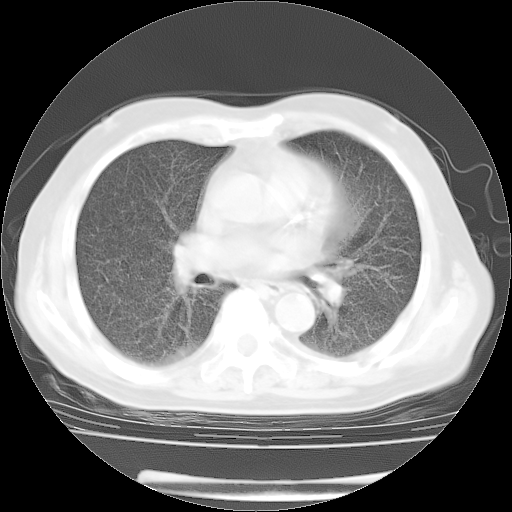

4月28日肺部CT——再次出现类似去年5月9日——透光度降低,“间质性”改变。

4月28日肺部CT——再次出现类似去年5月9日——磨玻璃样、间有“粟粒样”改变。